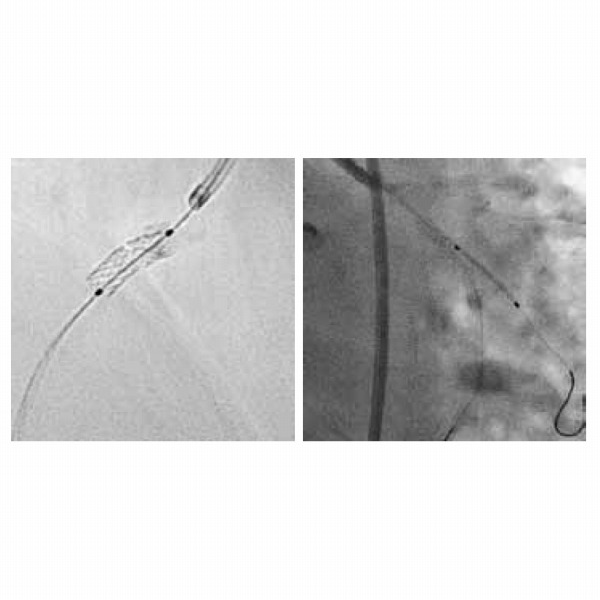

Artis oneは、シンプルでありながら、X線血管撮影装置の先駆者であるシーメンスの技術により、高い画質と効率的かつ医療施設、医師、および患者さんにとって快適なルーチン検査の両立を実現します。

●低被ばくでありながら、高精細な高画質です。